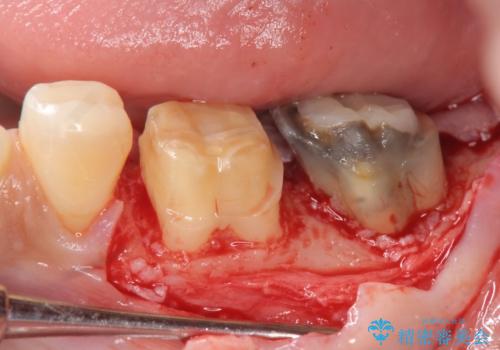

このままの状態でクラウンのやりかえを行うと高さが低く安定の悪いクラウンとなってしまうため、事前に歯周外科手術を行い歯ぐきを下げることで安定性の高いクラウンを製作する治療計画としました。

高さの低いクラウンはセメントが漏出しやすく脱離しやすいだけでなく虫歯の再発の可能性も高まってしまいます。

長期にわたりに安定した環境に整えることで、長く使える可能性を高めることができます。